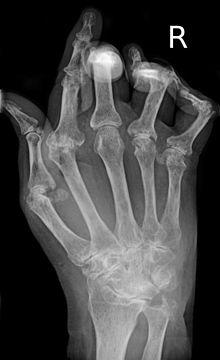

A hand severely affected by rheumatoid arthritis. This degree of swelling and deformation does not typically occur with current treatment.

As the pathology progresses the inflammatory activity leads to tendon tethering and erosion and destruction of the joint surface, which impairs range of movement and leads to deformity. The fingers may suffer from almost any deformity depending on which joints are most involved. Specific deformities, which also occur in osteoarthritis, include ulnar deviation, boutonniere deformity (also "buttonhole deformity", flexion of proximal interphalangeal joint and extension of distal interphalangeal joint of the hand), swan neck deformity (hyperextension at proximal interphalangeal joint and flexion at distal interphalangeal joint) and "Z-thumb." "Z-thumb" or "Z-deformity" consists of hyperextension of the interphalangeal joint, fixed flexion and subluxation of the metacarpophalangeal joint and gives a "Z" appearance to the thumb.[18]:1098 The hammer toe deformity may be seen. In the worst case, joints are known as arthritis mutilans due to the mutilating nature of the deformities.[22]